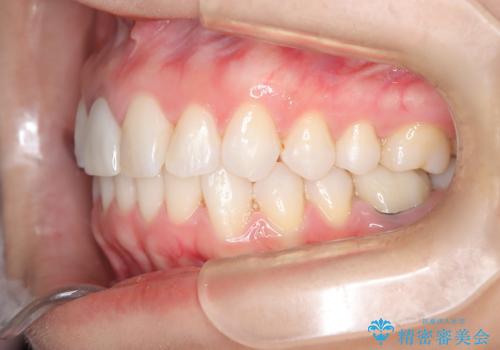

根管治療と並行して矯正を マウスピース治療

- 前歯のガタつき、変色を主訴に来院された患者様です。術前診査のCT撮影にて、変色した前歯の根の先に病巣があることが判明しました。そこで、マウスピースによる矯正治療と、前歯の根管治療、かぶせ物のやり直し治療を並行して行いました。